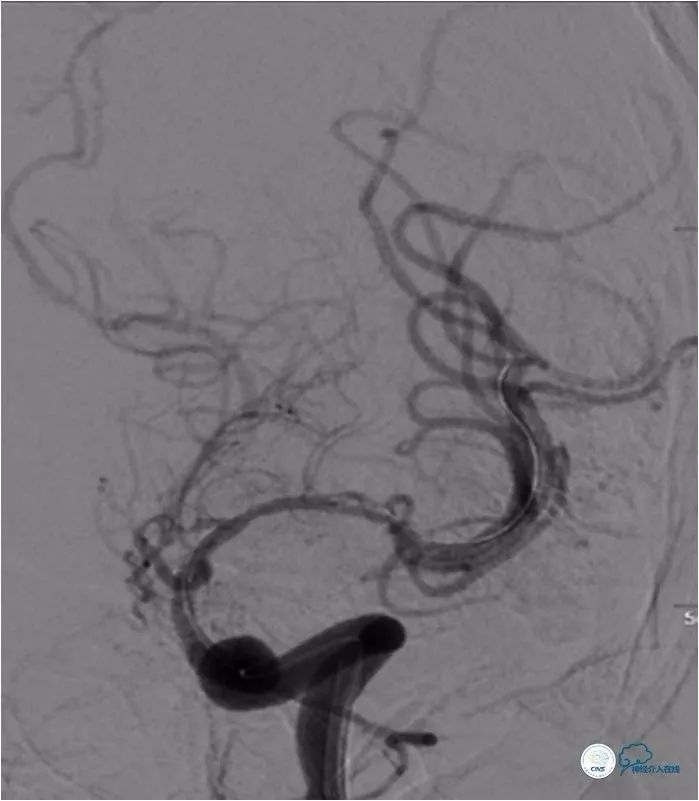

2017-11-20行左侧大脑中动脉M1段支架植入术(Gateway 2.0×15mm,Wingspan 3.0×20mm)(图2)。

图2